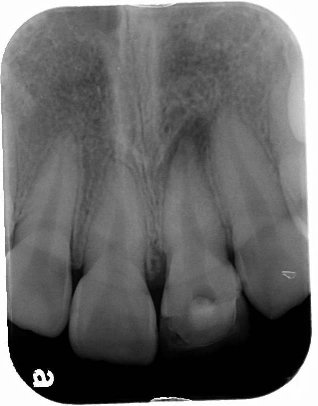

患者王小姐因左上正前牙疼痛劇烈前來求診 , 詳細問診之後, 了解該患者因多年前外傷造成前牙斷裂(見圖一) , 因當時只做緊急處理暫時用複合樹脂補起來 , 並未完整徹底根管治療 , 照數位X光(見圖二)後,發現左上正中門齒有根尖發炎的現象 , 初步診斷為慢性牙髓炎合併根尖骨質破壞 .

圖二 |